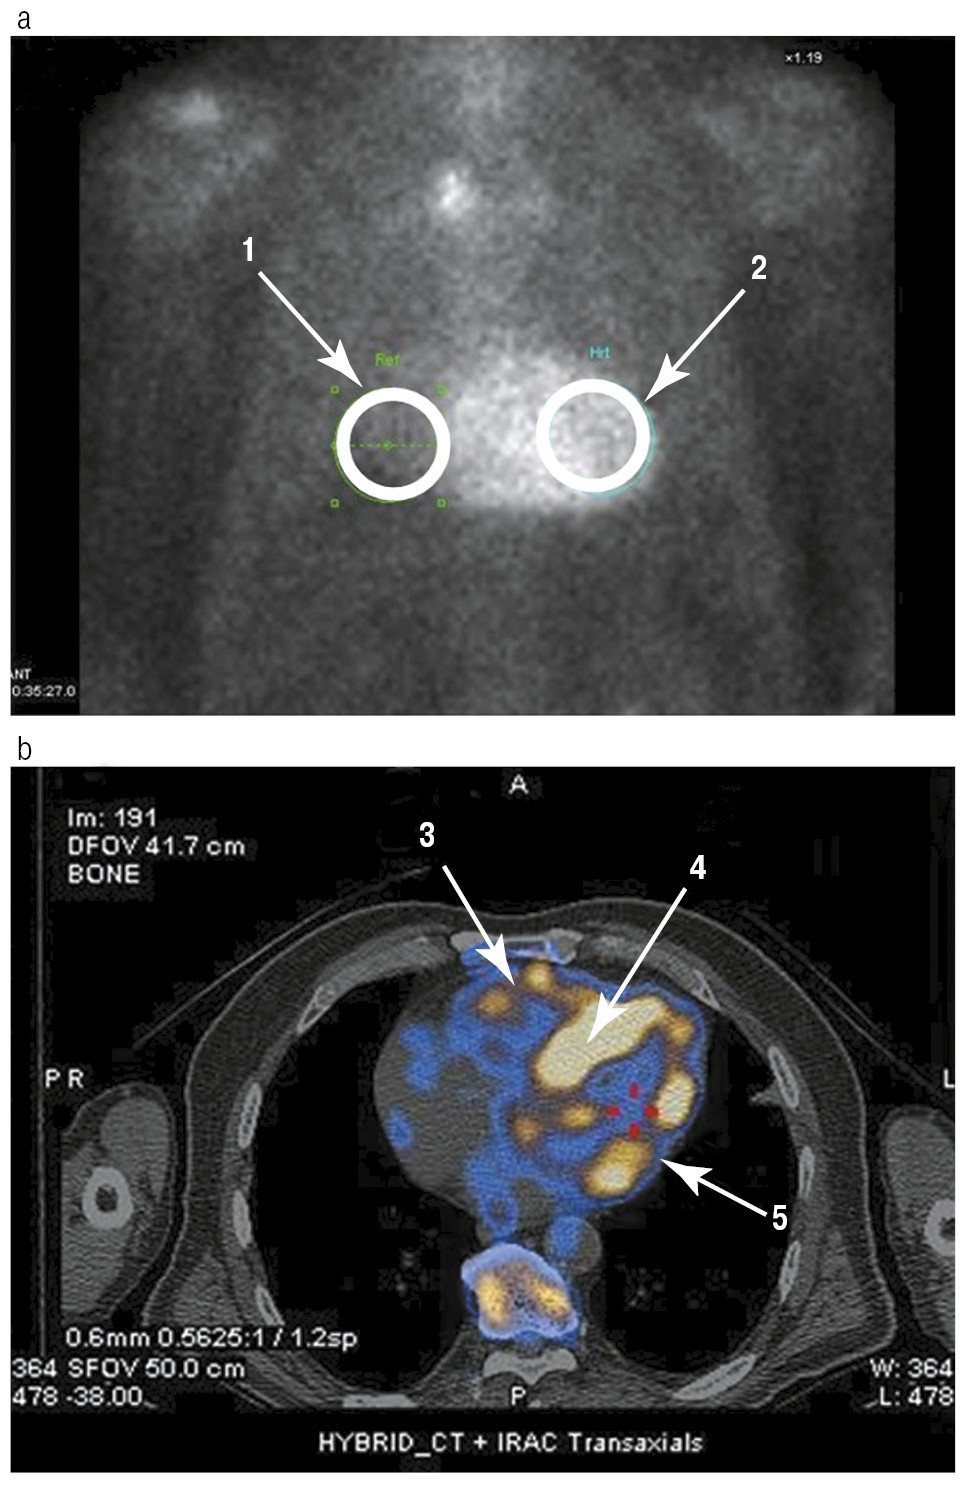

Рис. 3. Сцинтиграфическая картина у больного с ATTRwt:

a – планарное исследование – статическая сцинтиграфия в передней прямой проекции. Сравнение накопления РФП в области сердца (2) с контрлатеральной областью ребер (1). При вычислении соотношения – Grade 3 – видимое накопление, но его интенсивность выше, чем в костных структурах; b – гибридное исследование – ОФЭКТ: четко дифференцируются стенка ПЖ (3), ЛЖ (5) и межжелудочковая перегородка (4) [показано желтым цветом], накопление РФП в которых превышает накопление в ребрах.